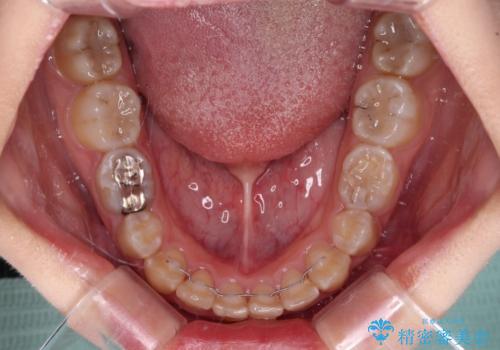

犬歯は歯根が太くて長いため、クロスバイトを改善するのは大変であることが多いですが、比較的スムーズに改善することができました。

インビザラインであったら、もっと期間はかかっていたような印象です。